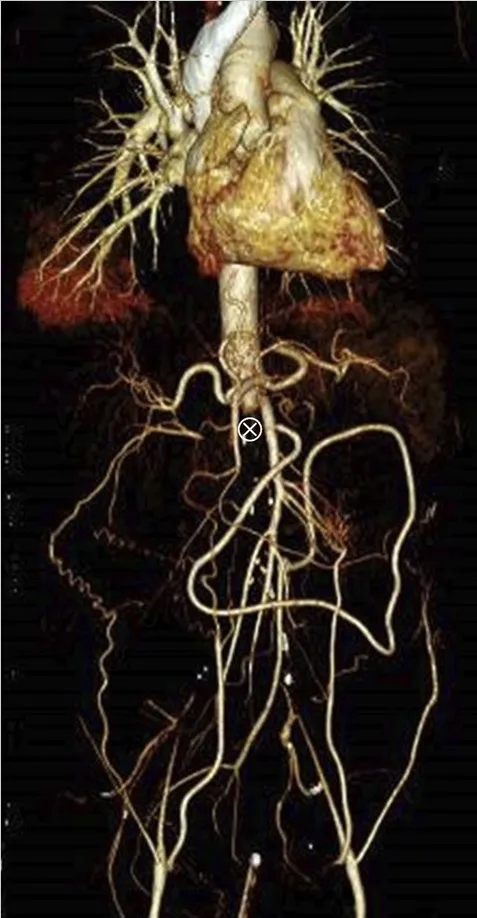

Paciente com dor lombar evoluindo com IRA e anúria